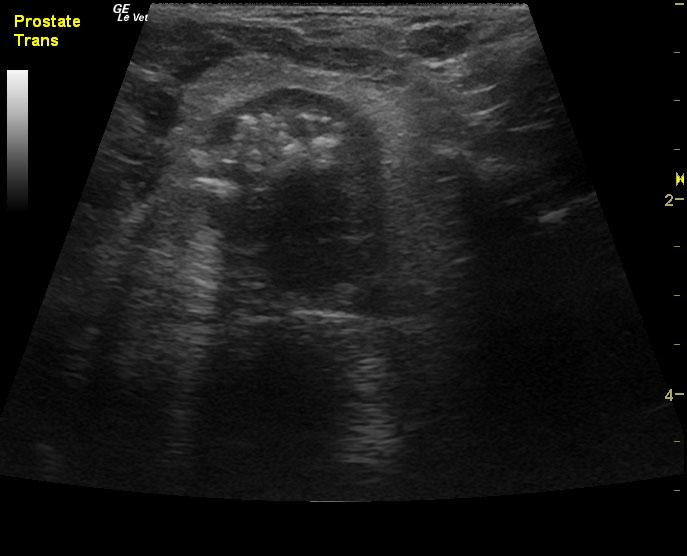

A 14-year-old neutered male Pomeranian dog was presented for evaluation of pollakiuria, diarrhea, inappetence, and lethargy. Abnormalities on physical examination included a painful, enlarged and symmetrical prostate, a very large and firm urinary bladder that could be expressed, and a grade III/VI heart murmur. On survey thoracic radiographs, calcification of the prostate gland was evident.